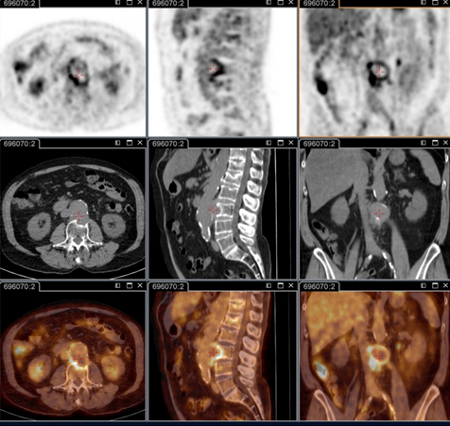

18F-fluorodeoxyglucose (FDG) PET/CT imaging

Test

Critical for identifying persistent focalised infections.[80]

Is able to decipher endocarditis, vascular infection, lymphadenitis, and osteoarticular infection; these conditions cannot be identified without this technique.

It is now part of the standard anatomical check-up in patients with persistent symptoms, and/or persistent elevated serology, and/or positive polymerase chain reaction on blood/serum, or any sample with clinical presentation not consistent with primary infection.[3]

It is specifically recommended for patients: with acute Q fever with persisting phase 1 IgG ≥1:800 and/or sign of bad evolution; with acute Q fever with a history of vascular graft or aneurysm; or with unexplained (phase 1 IgG ≥1:800) serology or clinical suspicion of a persistent infection.

Also useful for identifying infection in patients with vascular prosthesis and/or aneurysm, and identifying those who require surgery with resection of infected vascular tissues. [Figure caption and citation for the preceding image starts]: Q fever endocarditis diagnosed at PET scan: 18F-fluorodeoxyglucose PET/CT. In this asymptomatic patient with heart valve history with elevated serology, the PET scan diagnosed an aortic endocarditis on native valve with thoracic and lumbar aortic mycotic aneurysmsInstitut Hospitalo-Universitaire Méditerranée Infection (patient consent obtained) [Citation ends].

[Figure caption and citation for the preceding image starts]: Q fever aortic mycotic thoracic aneurysm diagnosed at PET scan: 18F-fluorodeoxyglucose PET/CT. In this asymptomatic patient with heart valve history with elevated serology, the PET scan diagnosed an aortic endocarditis on native valve with thoracic and lumbar aortic mycotic aneurysmsInstitut Hospitalo-Universitaire Méditerranée Infection (patient consent obtained) [Citation ends].

[Figure caption and citation for the preceding image starts]: Q fever aortic mycotic lumbar aneurysm diagnosed at PET scan: 18F-fluorodeoxyglucose PET/CT. In this asymptomatic patient with heart valve history with elevated serology, the PET scan diagnosed an aortic endocarditis on native valve with thoracic and lumbar aortic mycotic aneurysmsInstitut Hospitalo-Universitaire Méditerranée Infection (patient consent obtained) [Citation ends].

Result

positive for persistent focalised infection (e.g., heart valve, lymphadenitis vascular focus, lymph node, osteoarticular focus)